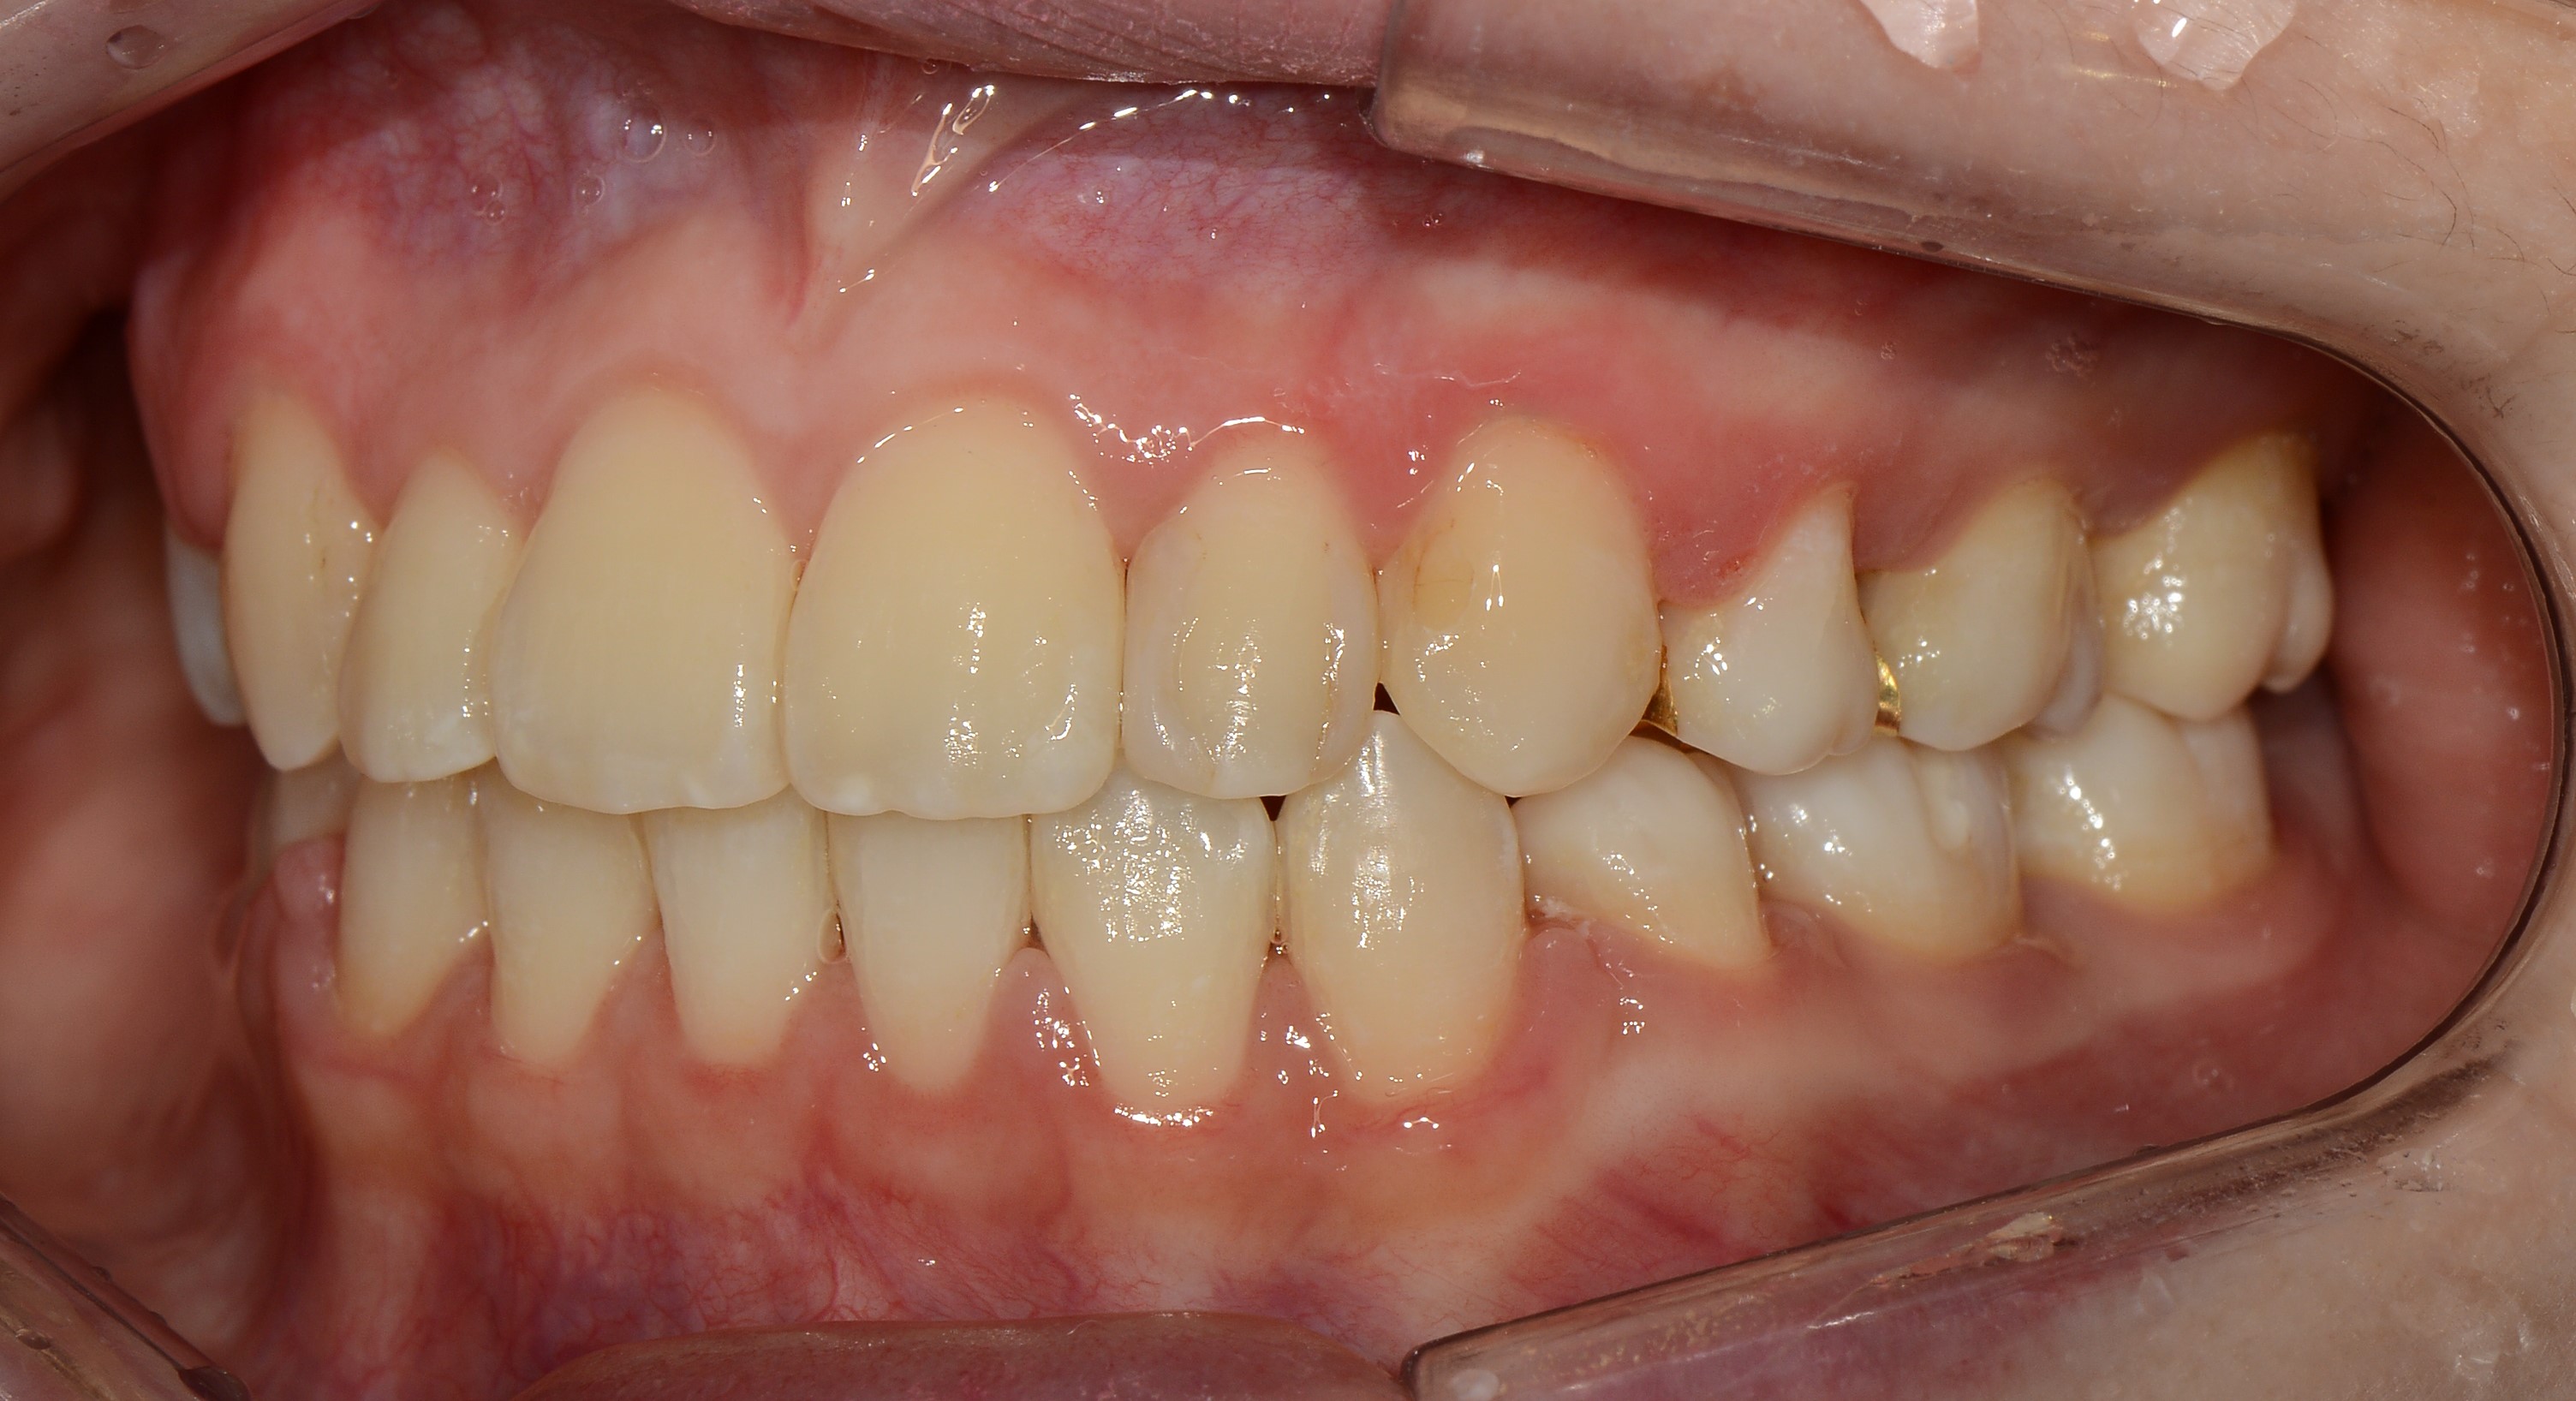

치료 후 사진입니다.